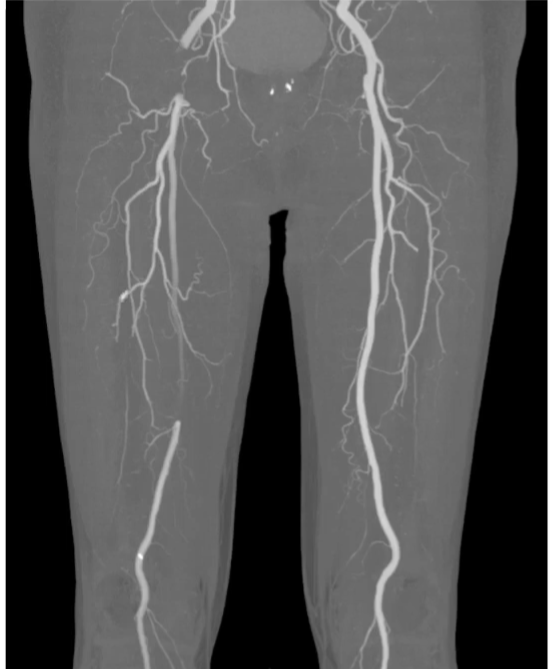

2. 응급실에서의 진단은 주로 Enhanced CT!!

- 조영 된 혈관이 하얗게 보이게 되는데, 뼈나 칼슘의 밝기와 비슷 밝기로 보이게 된다.

- 동맥 내막의 석회화 및 이로 인한 협착이 있을 경우 이를 혈류와 구분하기 어렵다.

- 따라서 CT영상의 음영을 조절하며 비교하거나, 비조영 CT 영상과 대조하여 석회화와 혈관 내 조영제를 구분하여 보는 것이 중요하다.